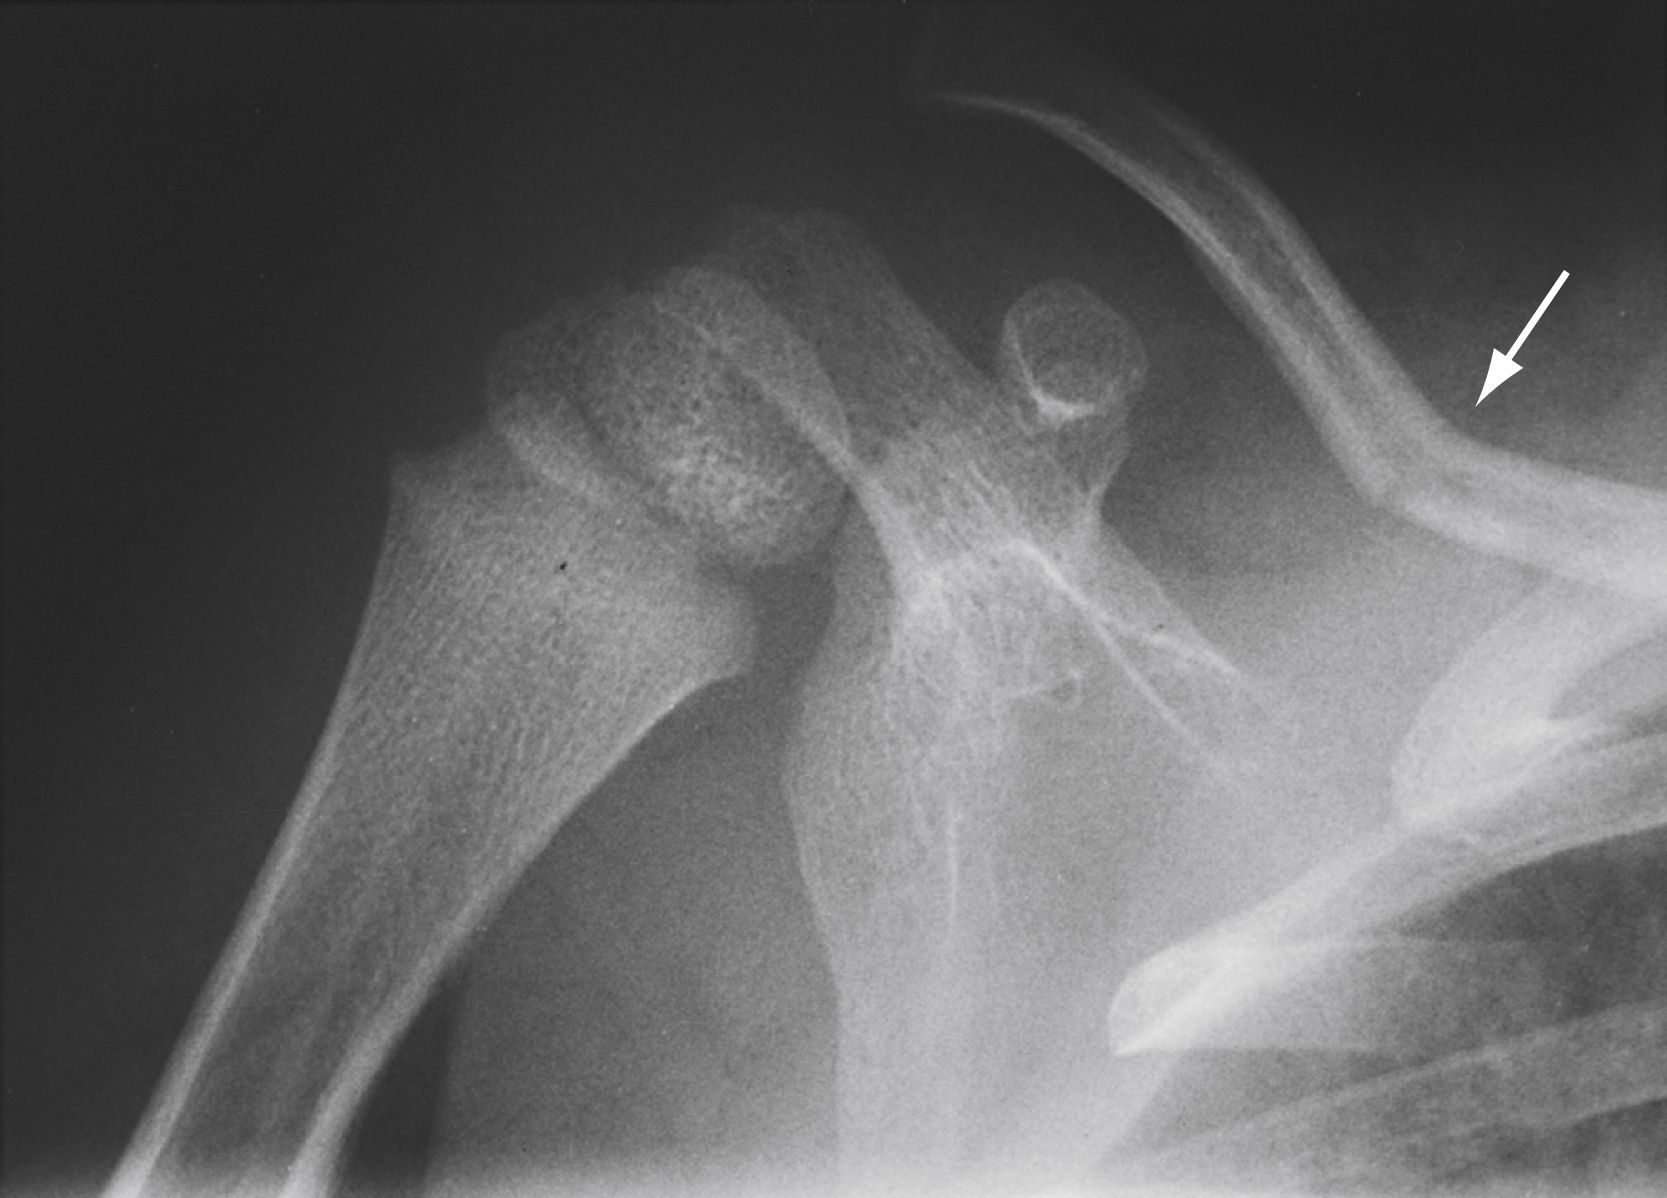

Diagnostic testing

Although diagnosed clinically, sternoclavicular dislocation requires radiological confirmation. Findings on standard anteroposterior, oblique, and specialized (40-degree cephalic tilt) SCJ views are challenging to interpret. These dislocations and associated injuries are best visualized by a chest CT angiogram ( Fig. 45.16 ). POCUS can be a useful bedside adjunctive test.

This computed tomography (CT) scan shows posterior dislocation of the right sternoclavicular joint (SCJ; arrow ) with compression of the superior mediastinum.

Courtesy Donald Sauser, MD.